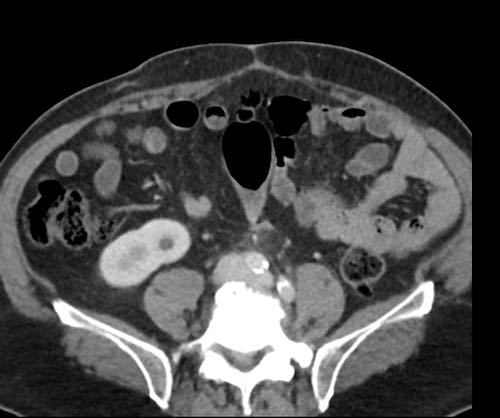

Cuộn xem ảnh CT

Ca lâm sàng 1

Cuộn qua các lát cắt.

Bạn có thể phát hiện tất cả các tổn thương cấy ghép phúc mạc không?

Bệnh nhân này đã được phẫu thuật và toàn bộ phúc mạc được ghi nhận phủ kín bởi các tổn thương u dạng kê.